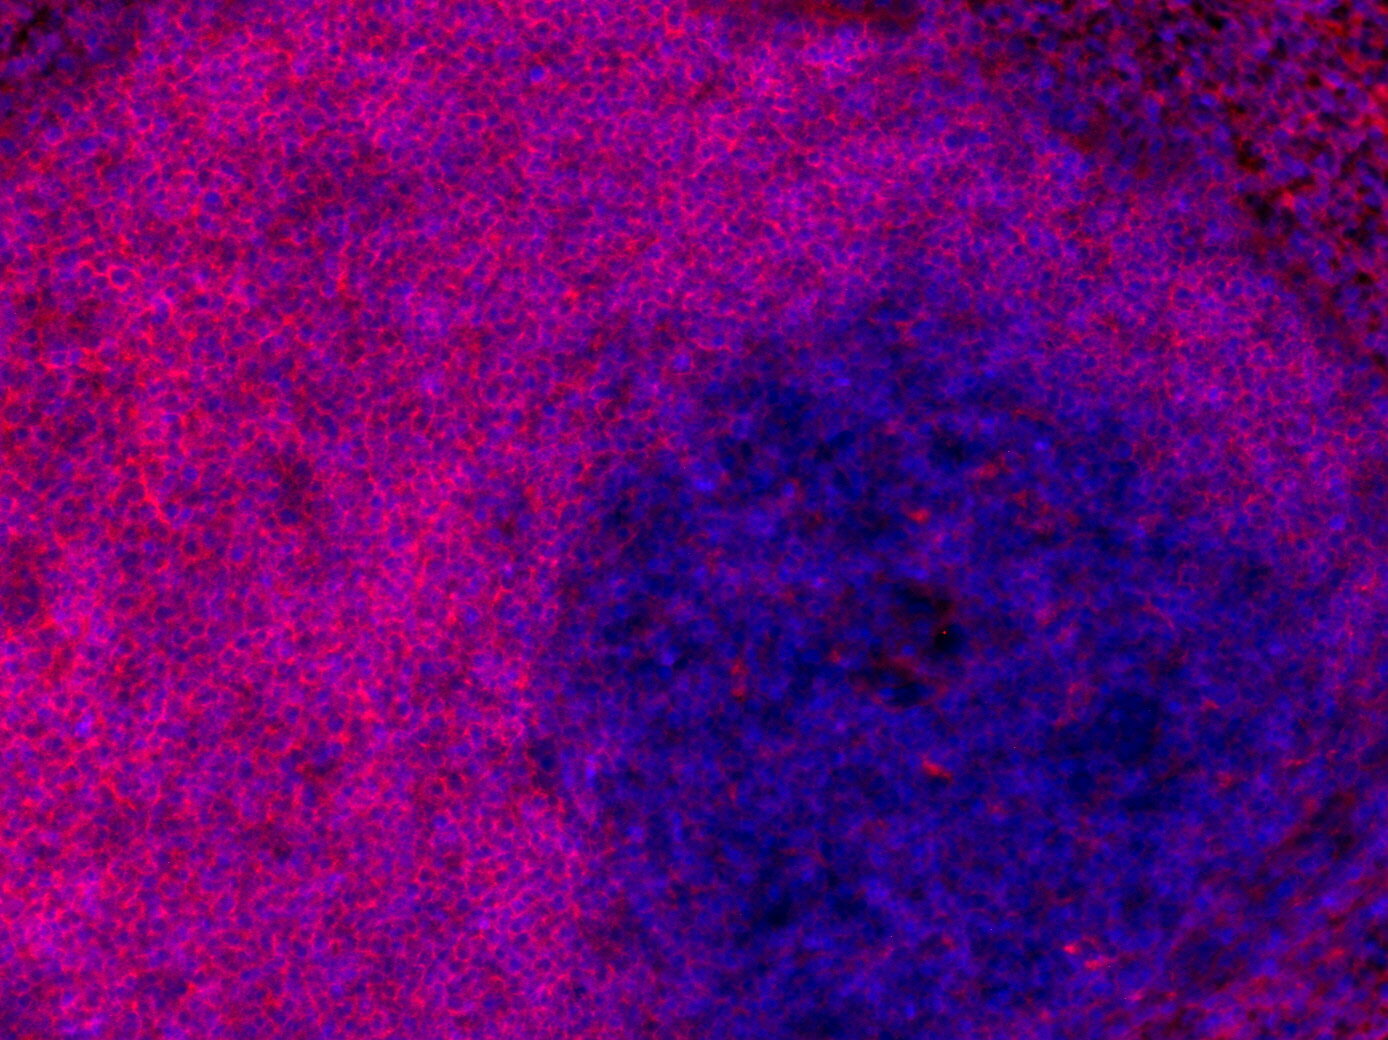

IHC: 1 : 200 gallery

IHC-Fr: 1 : 200 (see remarks) gallery

Chromogenic double staining for CD19 (DAB) and CD3e (RED) visualized T-cell and B-cell populations in the mouse spleen